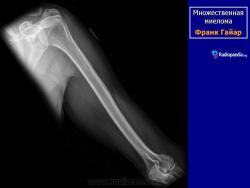

Рентгенологические проявления миеломы бывают классическими с четкими литическими очагами, окруженными ободком склероза, также характерен остеопороз различной степени выраженности, что часто приводит к патологическим переломам. В 25% случаев очаг поражения не выявляется при обычной рентгенографии, при помощи КТ и МРТ выявляют маленькие очаги поражения.

МИЕЛОМА, МНОЖЕСТВЕННАЯ МИЕЛОМА, МИЕЛОМНАЯ БОЛЕЗНЬ, СЕКРЕТИРУЮЩАЯ ЛИМФОМА, ПЛАЗМАЦИТОМА, БОЛЕЗНЬ РУСТИЦКОГО и т.д. – все это синонимы одного заболевания, которое обусловлено неконтролируемым ростом плазматических клеток, продуцируемым костным мозгом. Плазматические клетки, в свою очередь, являются конечной стадией дифференциации В-лимфоцитов – основного звена клеточно-гуморального иммунитета, основная функция которых – продукция иммунных белков – иммуноглобулинов IgG, IgA, IgM, IgE, IgD, участвующих в гуморальном иммунитете. Поэтому в норме костный мозг всегда содержит некоторое количество плазматических клеток. Однако, в случае их неконтролируемого роста увеличение количества плазматических клеток приводит к их сосредоточению в виде плазмацитомы в костном мозге, особенно в позвоночном столбе, тазовых костях, ребрах, плоских костях черепа, головках тазобедренных суставов, в результате чего нормальная костная ткань и костный мозг разрушаются. Очаги деструкции видны при рентгеновском исследовании, но, к сожалению, разрешающая способность рентгена позволяет выявить разрежение костной ткани, если порядка 30% ее уже разрушено. Миеломные клетки продуцируют иммуноглобулин одного вида (моноклональный), который при специфическом электрофоретическом исследовании сыворотки крови и мочи проявляется пиком, называемым М-градиентом, где М - означает моноклональный или миеломный. Отсюда происходит название болезни – миелома. Моноклональные белки (протеины), продуцируемые миеломными клетками, имеют измененную структуру, не выполняют функций иммунитета и называются «парапротеинами». Иногда они теряют какую-то свою часть и могут продуцироваться только моноклональные легкие цепи (белок Бенс-Джонса), или моноклональные тяжелые цепи.